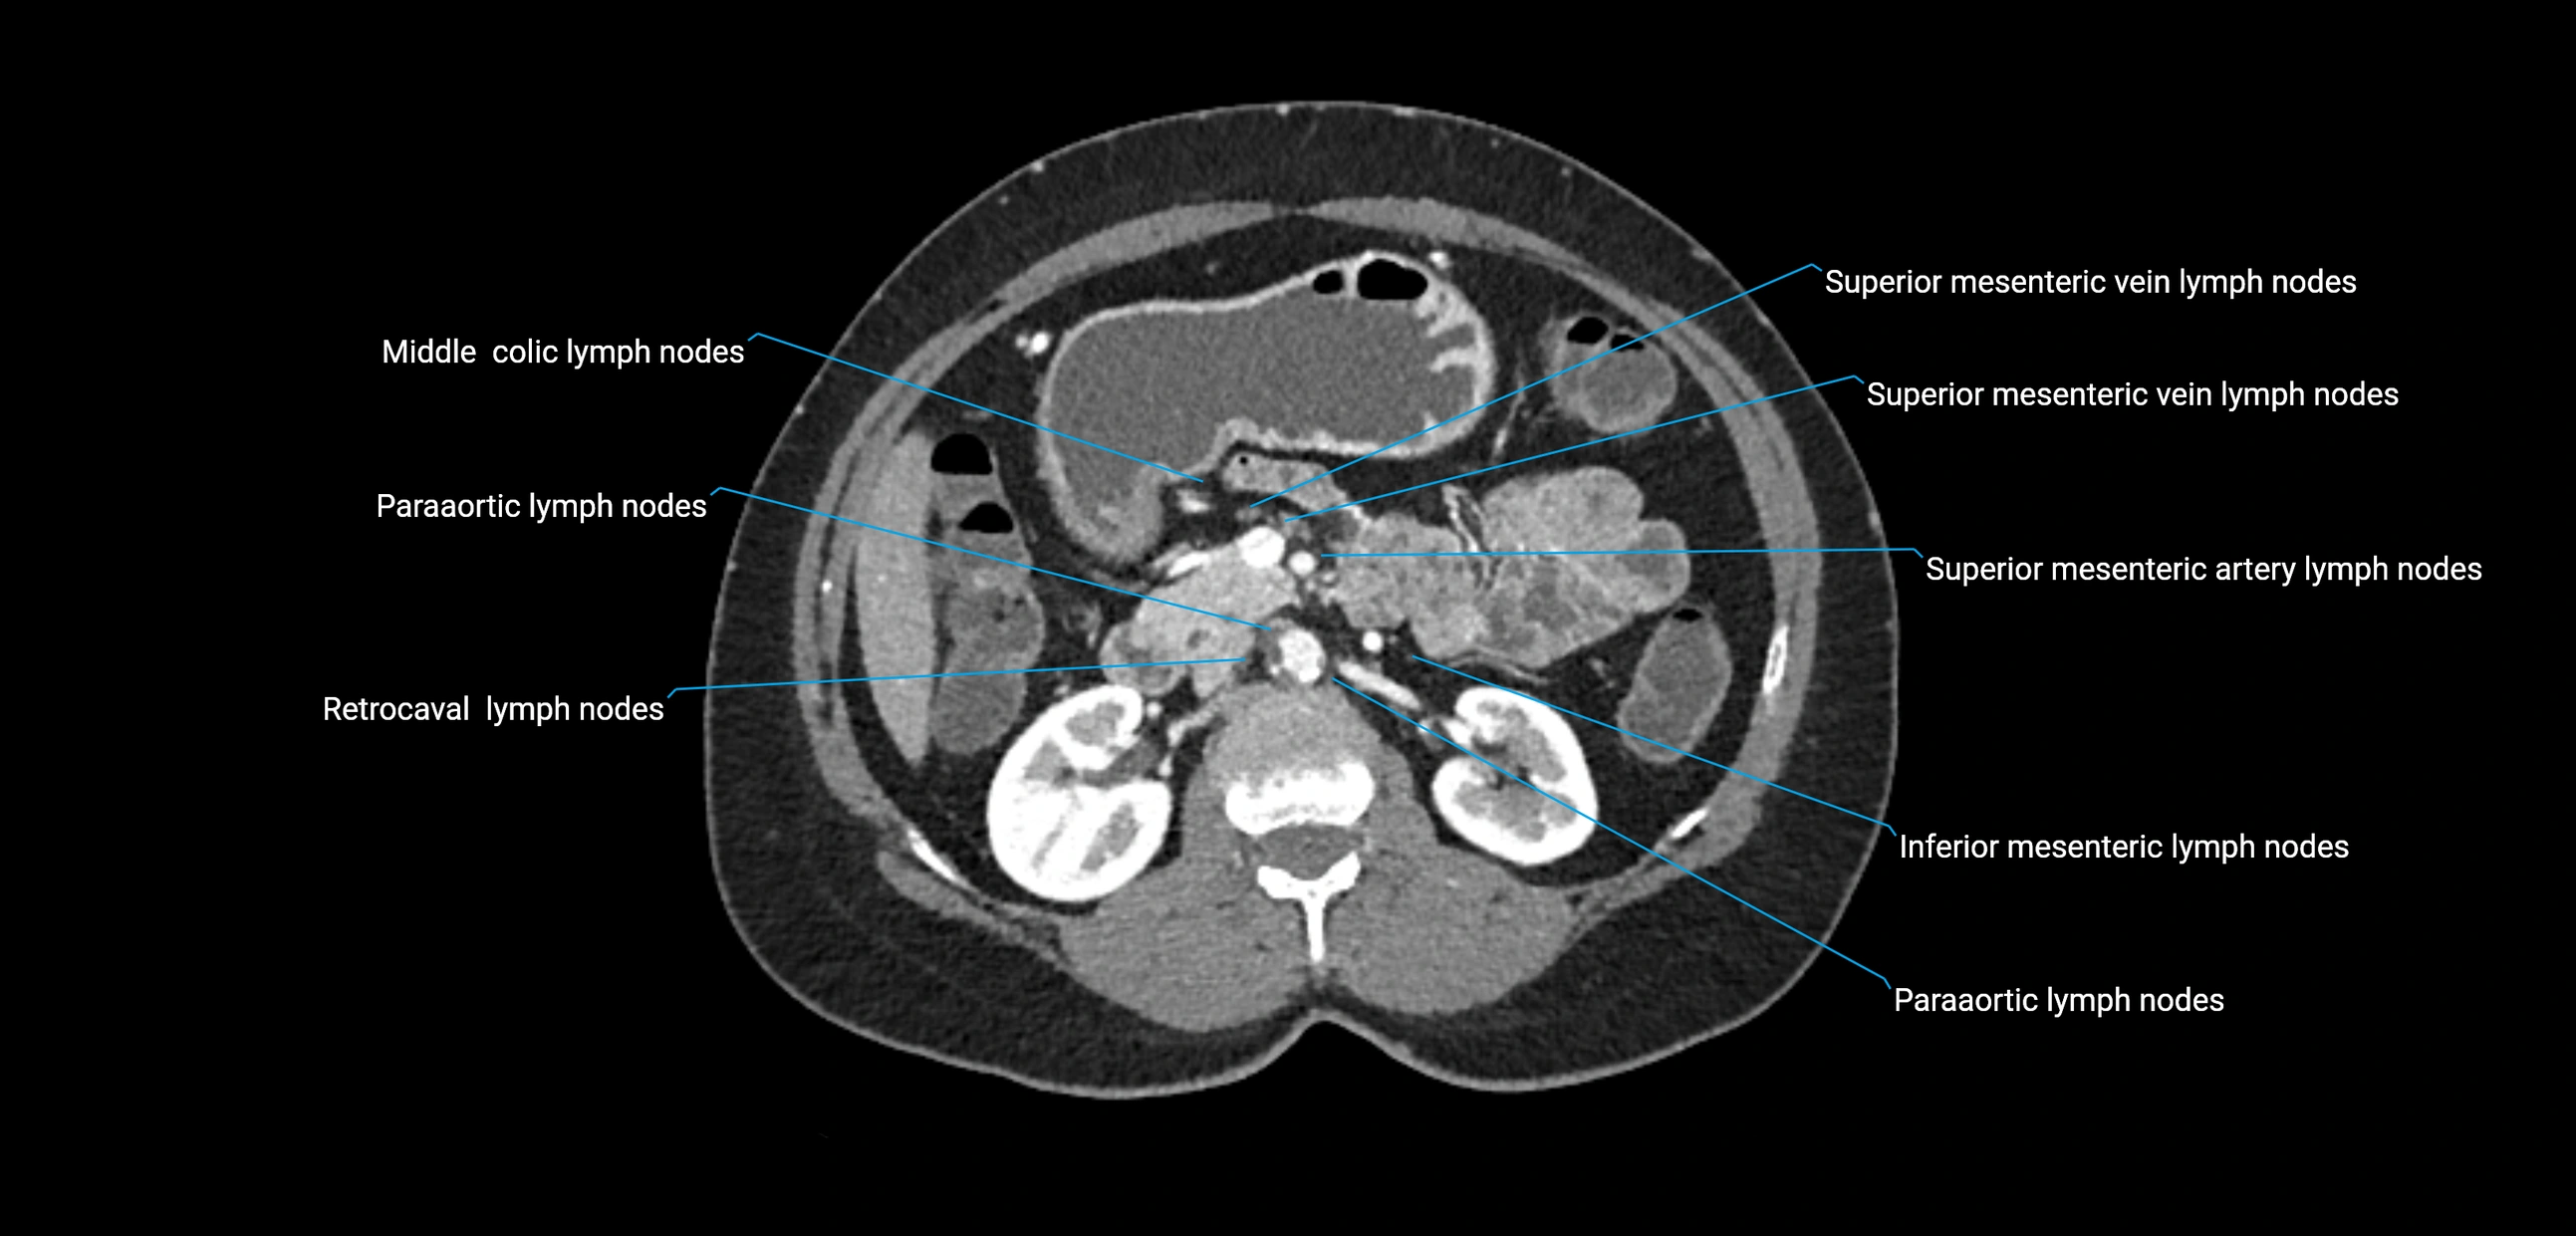

CT Appearance

CT Pre-Contrast:

• Nodes appear as soft-tissue density nodules adjacent to the aorta and IVC

• Calcification may be seen in chronic infections (e.g., tuberculosis)

CT Post-Contrast:

• Normal nodes enhance homogeneously

• Malignant nodes may show heterogeneous enhancement, central necrosis, or conglomerate formation

• Size >1 cm short axis is suspicious, though morphology and distribution are equally important

CT Venography (CTV):

• Demonstrates nodal encasement or compression of adjacent vessels (aorta, IVC, renal veins)

• Useful in staging testicular and ovarian malignancies

• Provides 3D reconstructions for retroperitoneal lymph node dissection planning